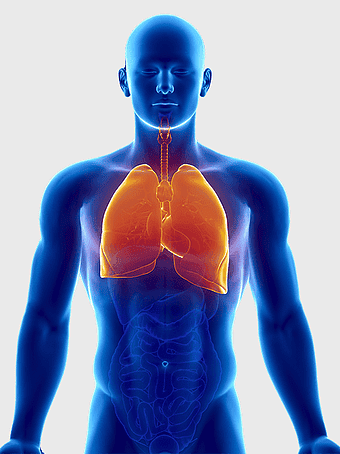

human lung anatomy, respiratory system illustration, heart and lungs diagram, bronchus structure, pulmonary function, thoracic cavity, medical imaging analysis -

lung illustration, cartoon lung, organ diagram, animated lung, respiratory system, human anatomy, medical illustration -

lungs illustration, respiratory system diagram, human lungs anatomy, pulmonary alveolus structure, bronchial tree visualization, trachea and bronchi, lung lobes detail -

lung organ, small lungs, respiratory system, pink trachea, human anatomy, medical illustration, pulmonary health -

Respiratory system anatomy, human breathing process, pulmonary alveoli structure, respiratory therapist training, respiratory health education, lung function diagram, respiratory disease prevention -

human lungs illustration, respiratory system anatomy, carina of trachea, blood vessel in lungs, pulmonary function, respiratory tract diagram, bronchial tree structure -

Lung Respiratory system, trachea and bronchus, pink lungs illustration, breathing anatomy, pulmonary health, respiratory function, medical education visuals